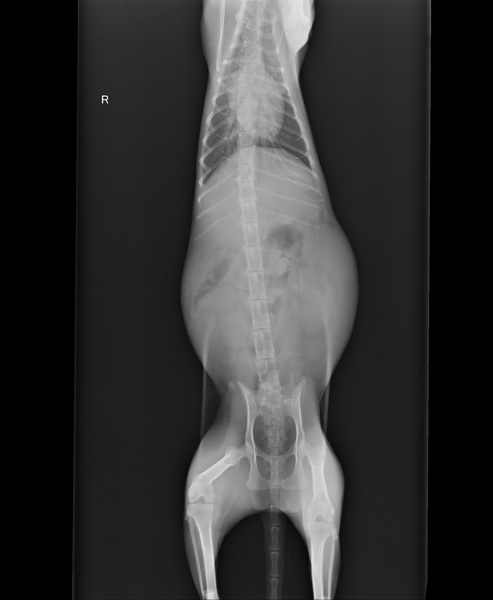

主題: 嚴重的貧血,腎衰竭以至於需引產保命的黑媽 申請者姓名: 李淑芬 花色: 申請日期: 2017-05-22 09:45:52 申請者部落格: 申請者臉書網址: 所在縣市/合作醫院: 高雄市/小新動物醫院 治療費用: 20000元 需求人數: 43人 已結案 (2024-06-01 13:29:45) 報名人員: 蔡汶萱 x4(已付款)、蹦蹦、ying x2(已付款)、kimi(已付款)、Bella Chen x2(已付款)、Js Lee(已付款)、Guan-Yi Li(已付款)、煌邵(已付款)、Carambar Liu(已付款)、楚荷 x3(已付款)、Norman Wu(已付款)、ray(已付款)、蝦(已付款)、aky(已付款)、張顥譯(已付款)、qousta(已付款)、mason(已付款)、陳哈君 x2(已付款)、懂懂沒(已付款)、詩詩 x2(已付款)、charlene x2(已付款)、貓貓奴隸(已付款)、sinice x4(已付款)、Mandy Chen(已付款)、小胖白、Athena Liu x5(已付款)、島本小姐(已付款)、a-song(已付款)、 候補人員: 動物病情說明: 前幾天我媽媽跑來跟我說她在家裡附近的早上菜市場看到一隻外來貓,全黑很瘦但肚子很大,感覺像懷孕了,餵牠卻不吃,精神狀況不是很好,我心想怎麼我餵時卻沒看到,於是我開始注意,經過一個禮拜終於在凌晨5點多的時候登到了牠,看到牠的第一個直覺是牠需要的是醫療不是食物,走路緩慢,眼睛有超多的分泌物,很瘦肚子卻很大,跟我媽形容得差不多,二話不說衝回家拿雞絲頭,搞了快一個小時,最後還請附近的魚販大哥拿魚網借我跟我一起抓到牠。送到醫院後,稍晚鐘醫生打來說黑媽身體狀況很不妙《我最討厭鐘醫師說出不妙這兩個字》

鐘醫師說

黑媽主要狀況是嚴重的貧血,腎衰竭,白血球很高,呼吸道感染,肚子方面從X光來看因為在腹腔內有團塊 ,原本懷疑有腫瘤或是子宮蓄膿,可是後來掃超音波發現原來是胚胎,但懷孕只會讓黑媽這些問題更嚴重,所以先等狀況穩定一點才能手術,而且他貧血很嚴重,甚至有可能要輸血,要趕快去找血了!動物近況說明: 黑媽住院期間狀況一直都不是很好,由於她懷孕導致她的嚴重貧血和腎衰竭更嚴重,加上她過瘦,所以必須先將她的體重和貧血狀況給穩住了才能做引產手術,期間醫生有打補血劑和加上帶去的營養品,好不容易有穩住黑媽的狀況,在5月2日時做了引產手術,做完手術後我有帶些補品曲給黑媽,希望手術部會讓他的狀況變不好,經過幾天觀察,醫生說黑媽的腎衰竭確定是永久的了,而她也不太能自行造血,所以我接回家安寧照顧時,每天都要打200西西的皮下點滴,而每禮拜就要去醫院打一劑造血針,目前黑媽一個人獨自在個人房裡,我暫時關她,想說讓她先適應一下家裡,雖然她很兇不親人,但這幾天用浴巾包裹她打皮下狀況都還算穩定,這次很謝謝小新動物醫院鐘醫師和助理們的幫忙照顧,黑媽的醫療費用還望大家多多幫忙,謝謝!